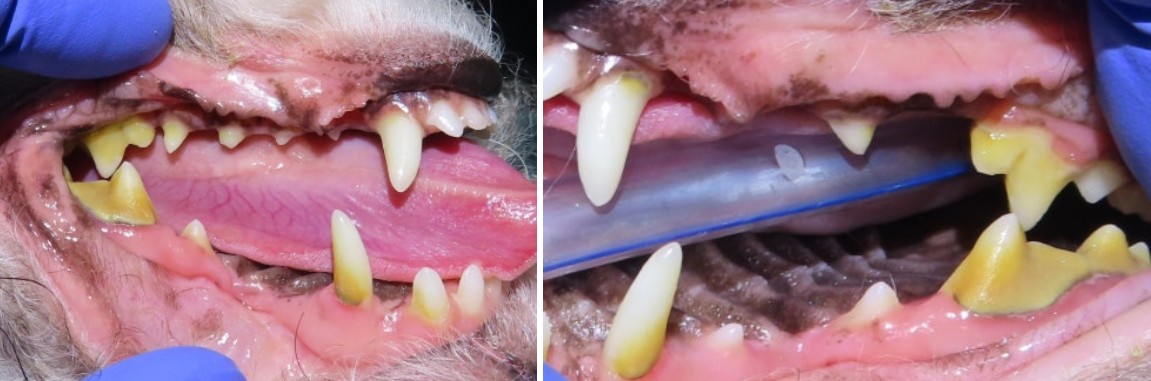

최근 서울 강북구 쌍문동 동물병원 비아츠에는 입가 염증이 반복되는 말티푸 아이가 내원했고, 정밀 방사선 촬영 결과 양측 상악 제1대구치(M1)에서 치내치가 확인되었습니다.

겉으로 보면 단순한 깊은 홈처럼 보일 수 있습니다.

구각염 반복

음식 섭취 시 불편

특정 부위 저작 회피 단순 치주염으로 보기에는 반복 양상이 이상했습니다.

강북구 쌍문동 동물병원 비아츠에서는 양측 상악 M1을 치근 분리 후 단계적으로 제거하는 방식으로 발치를 진행했습니다.

대구치는 뿌리가 2개로 나뉘어 있고 치조골 소실이 동반된 경우 난도가 높은 치아입니다.

치근을 하나씩 분리하여 제거하고 잔존 치조골을 정리한 뒤 조직을 긴장 없이 봉합하는 방식으로 마무리했습니다.